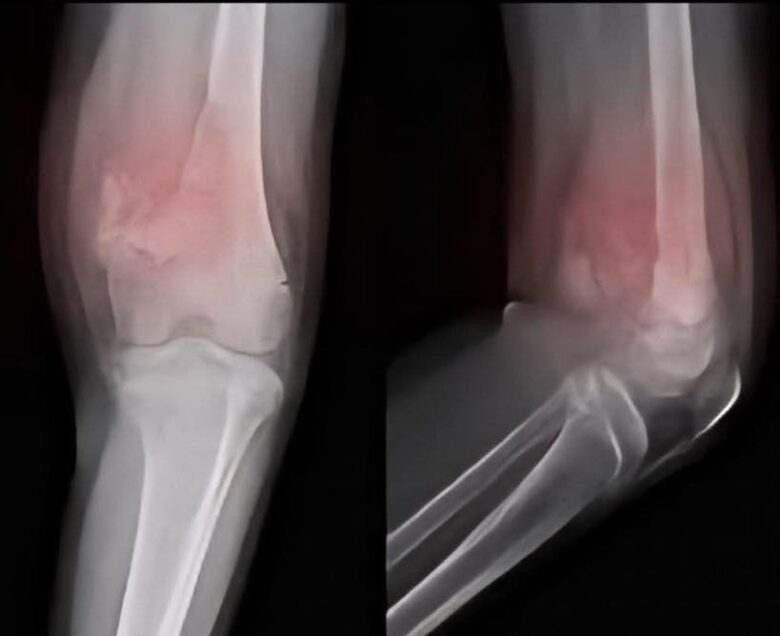

3. Fraturas sem causa aparente

Os ossos afetados tornam-se mais vulneráveis e podem se quebrar facilmente, mesmo após traumas leves ou na ausência de qualquer motivo aparente.

4. Como é feito o diagnóstico do câncer ósseo?

O diagnóstico geralmente envolve exames de imagem, como raios-X, tomografias ou ressonâncias magnéticas, além de biópsias.